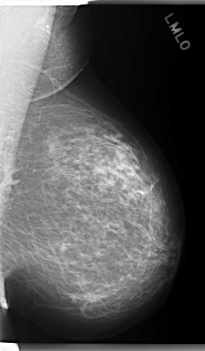

C_0286_1.LEFT_MLO

C_0286_1.LEFT_CC

LEFT_MLO LINES 5960 PIXELS_PER_LINE 3480 BITS_PER_PIXEL 12 RESOLUTION 50 NON_OVERLAY